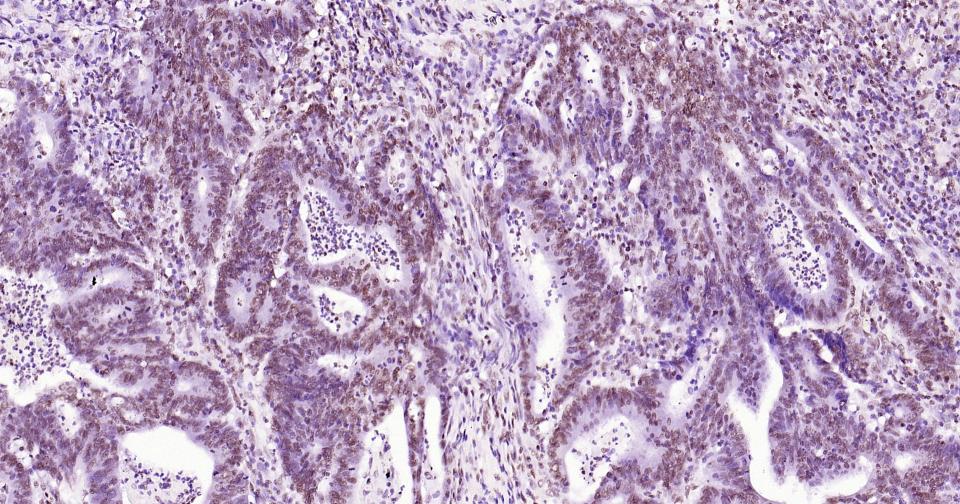

产品细节图片27

P‌‌araformaldehyde-fixed, paraffin embedded Human Colon Cancer; Antigen retrieval by boiling in sodium citrate buffer (pH6.0) for 15 min; Antibody incubation with Histone H3 Monoclonal Antibody, Unconjugated (ascites of bsm-33042M) at 1:1500 overnight at 4°C, followed by conjugation to the bs-40296G-HRP and DAB (C-0010) staining.